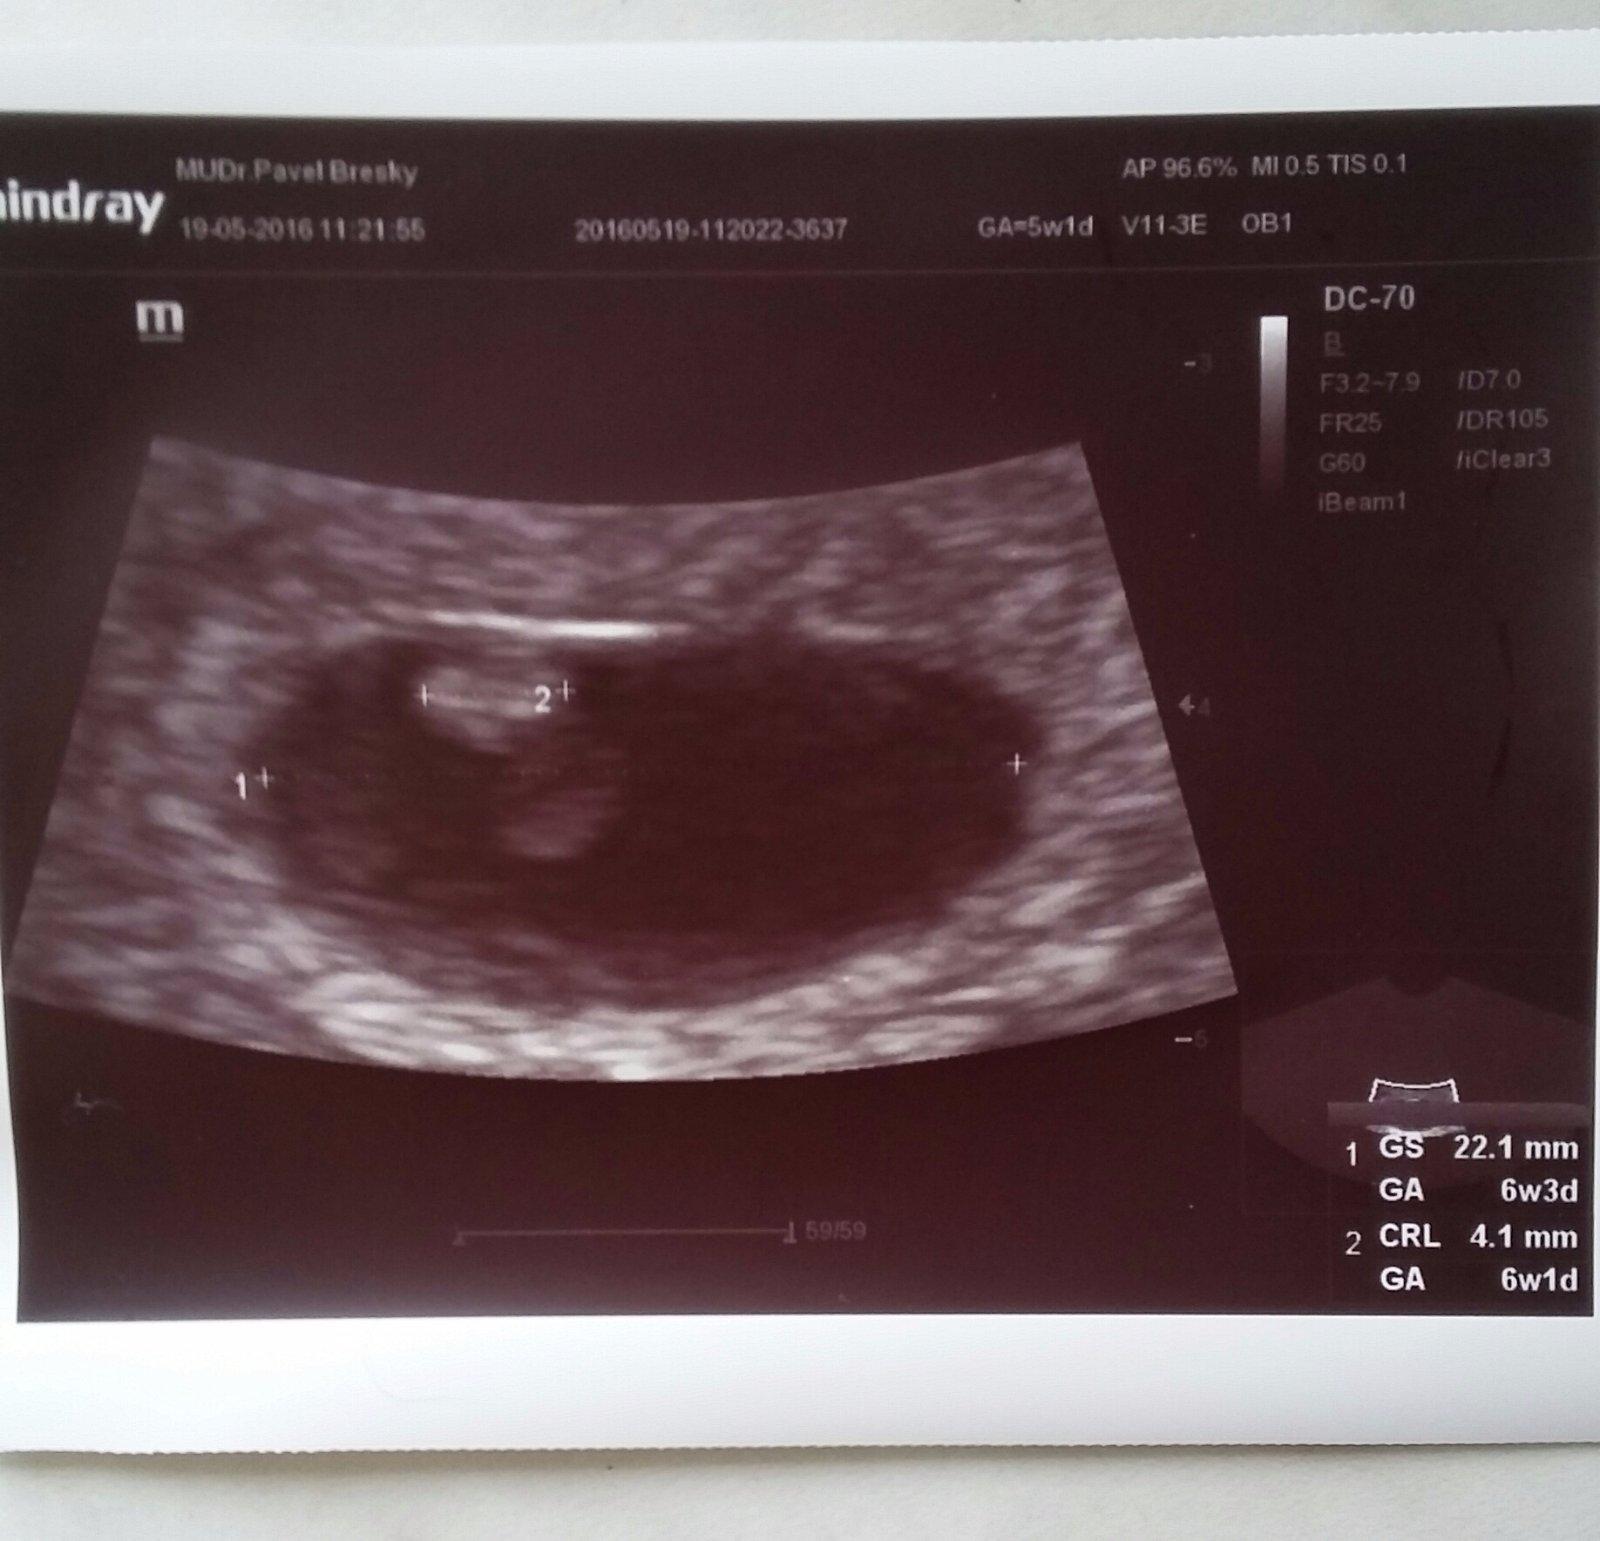

@tehulka1167 no ten je úžasný,a srdíčko tlouklo jak o závod,viď?Mooc ti to přeju,fakt 🙂

@pozi ano,srdicko blikalo 🙂